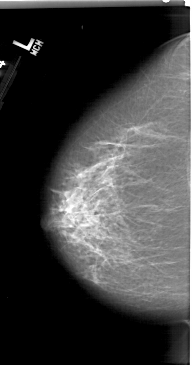

A_1411_1.LEFT_MLO

LEFT_MLO LINES 6751 PIXELS_PER_LINE 3601 BITS_PER_PIXEL 12 RESOLUTION 43.5 NON_OVERLAY